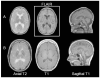

Leukodystrophies are a heterogeneous group of disorders associated with abnormal central nervous system white matter. The clinical features invariably include upper motor neuron signs and developmental regression with or without other neurological manifestations. The objective of this study was to characterize clinically and genetically a new form of childhood-onset leukodystrophy with ataxia and tremor. We recruited seven French-Canadian cases belonging to five families affected by an unknown form of childhood-onset leukodystrophy. Genome-wide scans (GWS) were performed using the Illumina Hap310 or Hap610 Bead Chip to identify regions of shared homozygosity that were further studied for linkage with STS markers. All cases presented between the ages of 1 and 5 years with spasticity along with other upper motor neuron signs, prominent postural tremor, and cerebellar signs. Though motor regression is a constant feature, cognitive functions are relatively preserved, even late in the course of the disease. The higher frequency of founder diseases in the French-Canadian population and the segregation in pedigrees are suggestive of a recessive mode of inheritance. By homozygosity mapping, we established linkage to a 12.6-Mb SNP-haplotyped region on chromosome 10q22.3-10q23.31 (maximum LOD score: 5.47). We describe an autosomal recessive childhood-onset leukodystrophy with ataxia and tremor mapping to a 12.6 Mb interval on chromosome 10q22.3-10q23.31. Identification of the mutated gene will allow precise diagnosis and genetic counseling and shed light on how its perturbed function leads to white matter abnormalities.